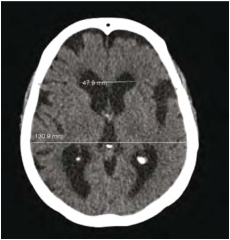

למבוגרים אשר מפתחים הידרוצפלוס בשנות חייהם המתקדמות יש כנראה יותר מנגנוני פיצוי אשר מונעים עלייה מסוכנת בלחץ התוך-גולגולתי מאשר לילדים וההידרוצפלוס מתפתח אצלם יותר באיטיות. הידרוצפלוס כרוני הוא מצב המוגדר הדמייתית בבדיקות טומוגרפיה ממוחשבת (CT ,Computed Tomography) ו/או תהודה מגנטית (MRI ,Magnetic Resonance Imaging) על ידי אומדן הגדלת החדרים. אחד המדדים לגודל החדרים הוא Evans index, היחס בין רוחב הקרניים המצחיות לרוחבו המירבי של המוח. בהידרוצפלוס כרוני מדד זה יהיה גדול מ-0.3 (תמונה מספר 1). מדדים הדמייתיים נוספים הם הרחבת הקרניים הרקתיות, שינויי אות או בצקת סביב חדרי המוח ושינויים באות הזרימה בתעלה (Aqueductal/fourth ventricular flow void) (תמונה מספר 2), בנוכחות לחץ CSF תקין או מעט גבוה. התמונה ההדמייתית מלווה בהתפתחות של תסמינים קליניים דומים, ללא קשר לגורם הראשוני.

- מדדים הדמייתיים הכוללים 0.3<Evans index, שינויי אות סביב החדרים, הגדלת קרניים רקתיות ועוד.